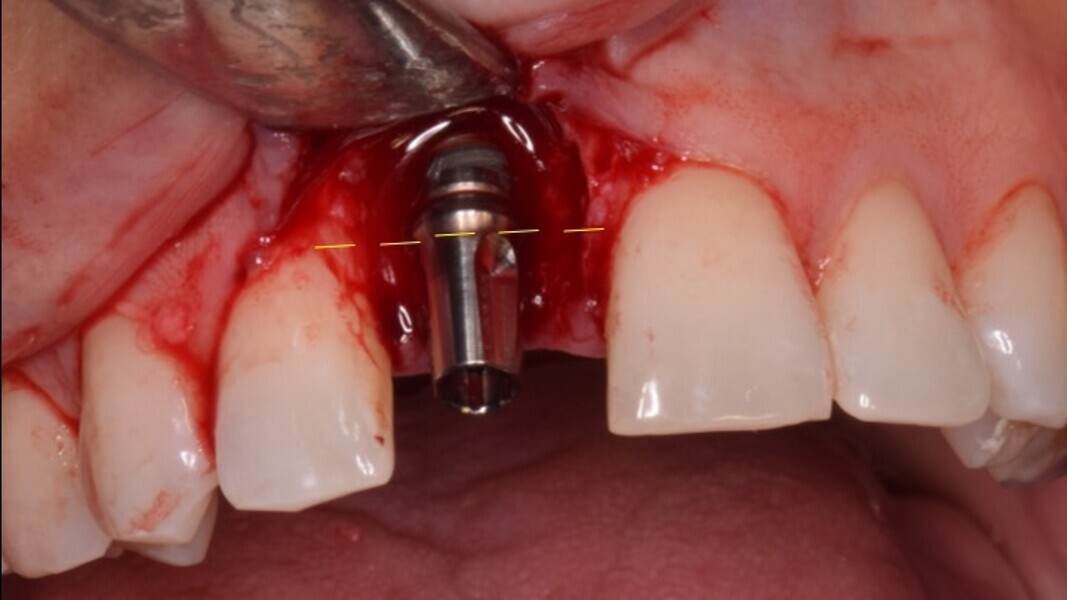

Figura 7. Implante de conexión interna insertado 2 mm por debajo de la cresta ósea, independientemente del defecto existente y a 55 Nw. Al no existir margen vestibular, tomamos como referencia los dos picos óseos de las papilas y entre ellos trazamos una línea imaginaria que los una enterrando el hombro unos 2 ó 3 mm por debajo de ella.